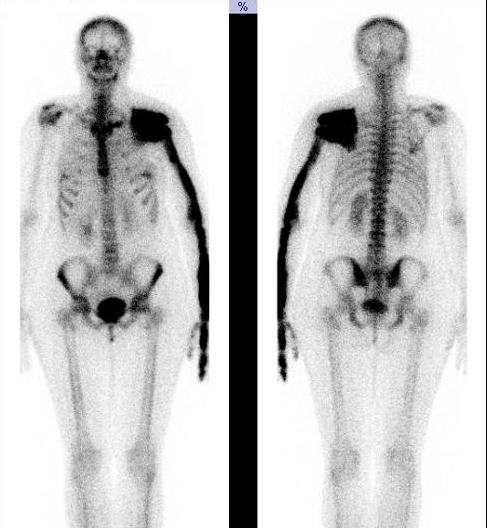

7M. Diagnosis?

Legg-Calvé-Perthes disease - an idiopathic avascular necrosis (AVN) of the growing femoral epiphysis seen in children.